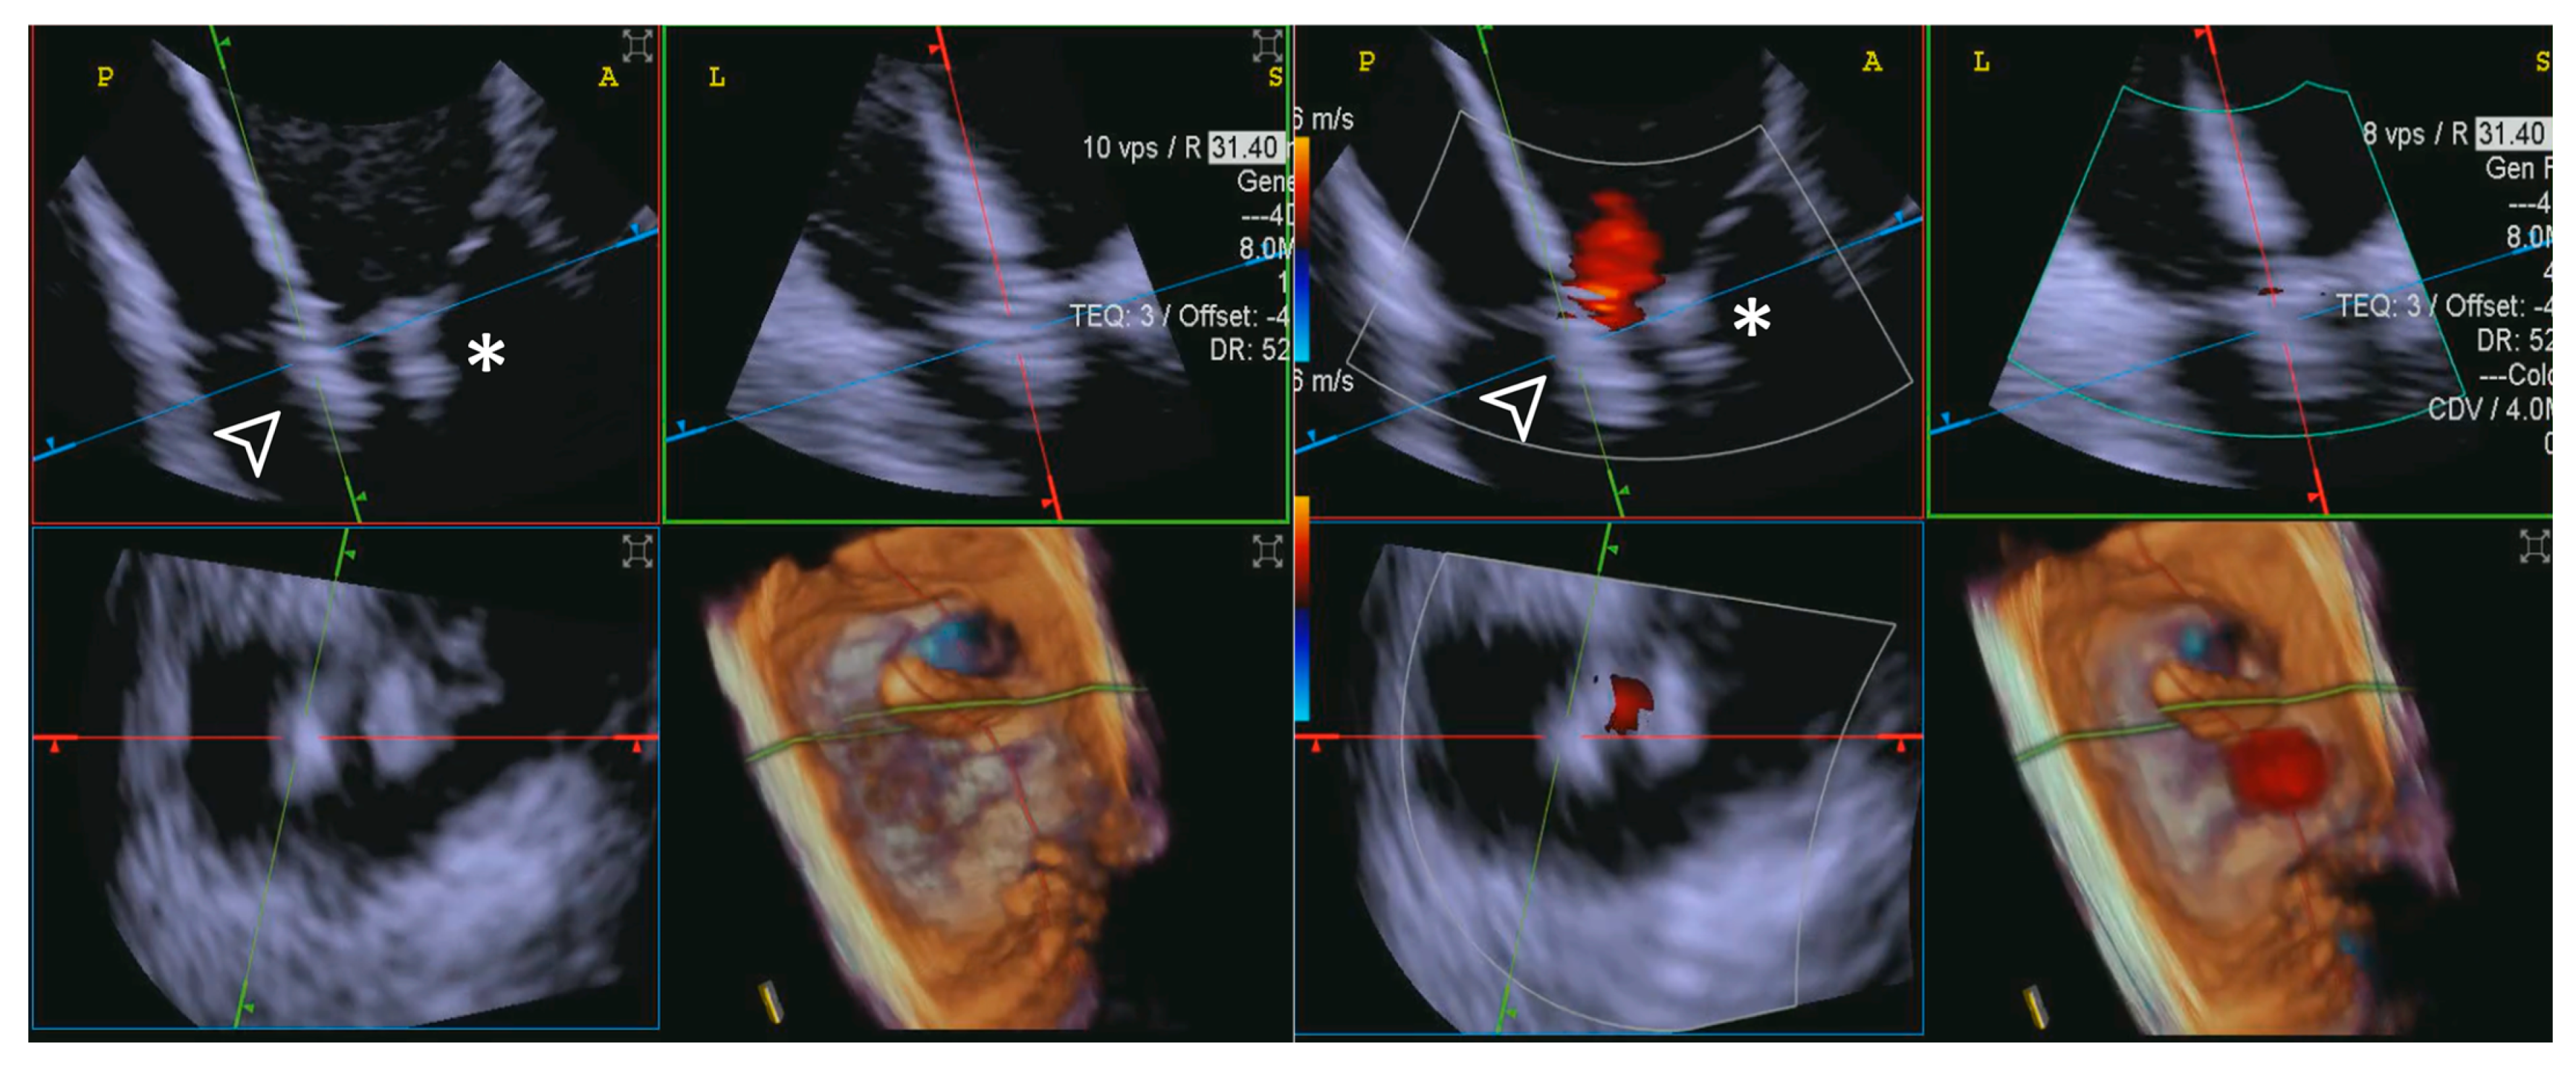

- Step number 2: identification of the target lesion.

- Step number 8: evaluation of residual regurgitant jets.